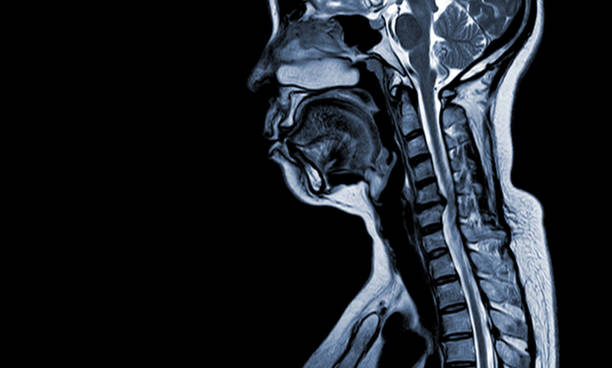

허리디스크는 디스크가 변형되고 압박이 발생하는 위치와 정도에 따라 다양한 증상이 나타날 수 있습니다.

그리고 허리디스크의 치료법은 환자의 증상과 디스크의 상태에 따라 다양하게 적용됩니다.

이처럼 증상을 제대로 파악하고 그에 맞는 치료법을 적용해야 합니다.